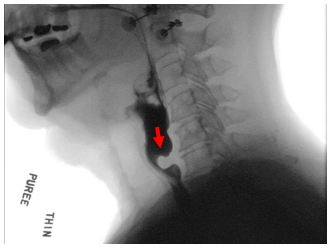

A barium esophagram or modified barium swallow study (x-ray swallowing tests) allow clinicians to evaluate the function of the CP muscle. Food or liquid residue is seen in the throat after a patient swallows due to the incomplete passage of material through the upper esophageal sphincter. A test called an esophageal manometry can also be performed to measure the muscle contraction force and coordination along the entire esophagus during swallowing.Treatment for Cricopharyngeal Dysfunction

Cricopharyngeal Bar